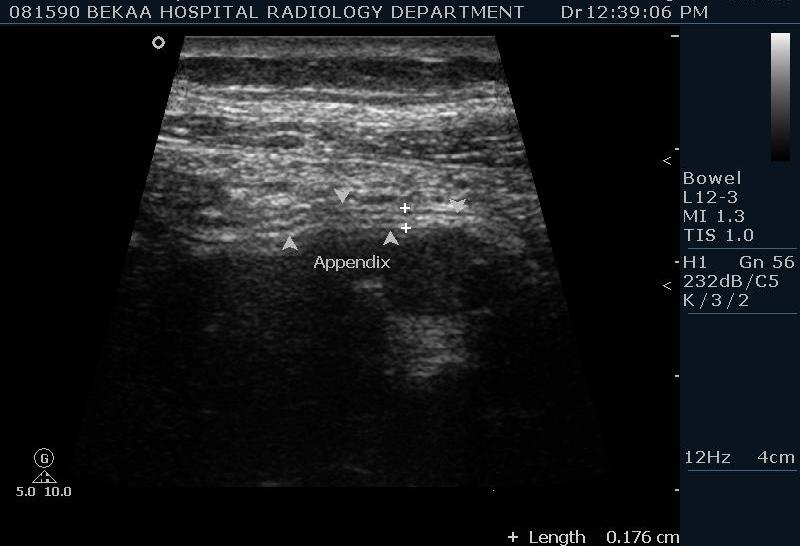

Диагностика острого аппендицита по УЗИ: очень актуальная тема; УЗ аппараты практически есть во всех клиниках; метод доступный и не сложный; главное владеть правильной техникой. Не буду загружать лишней теорией и разными ссылками; поделюсь практическим опытом. У меня линейный датчик 3-12 мегагерц с плавающей частотой; аппарат Филипс HD 11, всегда включаю соно-КТ (9800 цифровых каналов) и гармонику когда смотрю кишечник. Нормальный аппендикс видеть можно; но вопрос зачем??? Как правило, если при наличии достаточного опыта аппендикс не виден; значит скорей всего аппендицита нет. Когда "идешь" на аппендицит то главное по началу набраться терпения и......хорошая компрессия! По началу надо минут 10-15; потом когда появится достаточный опыт; за 2-5 минут можно справится и получить отличную визуализацию. Мочевой пузырь лучше опорожнить; часто он приподнимают тонкий кишечник и может закрыть "окно" через которое будет видно апендикс. Сначала находим слепую кишку потом находим илео-цекальное соединение;

после начинаем производить хорошую компрессию датчиком попрося пациента сообщить в какой точке боль наиболее выражена; медленными движениями датчика сканируем область наибольших болевых ощущений и как правило находим утолщенный отросток. Лучше начинать с поперечной визуализации и идти к верхушке аппендикса что бы убедится что это аппендикс и он заканчивается, а не тонкая кишка (которая если и закончится то только переходя в слепую); потом надо аккуратно развернуть продольно датчик и посмотреть от верхушки аппендикса к слепой. Норма диаметра: 3-4 мм; 5-6 мм под вопросом (клиника решает; но я в катаральный аппендицит не верю); 7-8 мм и больше, не компремируемый (фиксированный отросток)-острый аппендицит! Помимо наличие утолщенного аппендикса; признака "бычьего глаза" (bull-eye sign) при поперечном сканировании; надо обращать внимание на присуствие аппендоколитов в просвете; деструкцию стенки и свободной жидкости в зоне интереса.